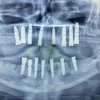

علاج الزرع السني

التهاب ما حول الزرعة السنية (Periimplantitis)

التهاب الغشاء المخاطي حول الزرعة السنية (Peri-İmplant Mukozitis)